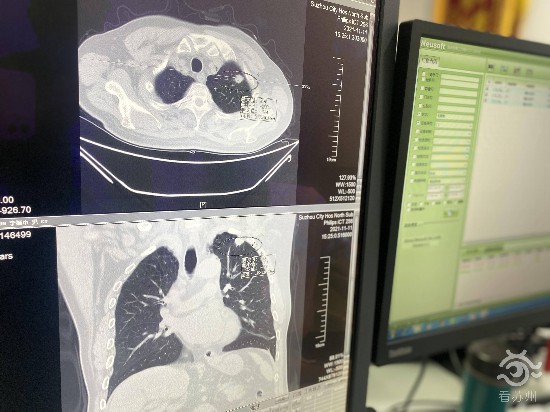

在病房,我们见到了正在住院康复中的李振中,66岁的他在前段时间的体检中被告知肺部出现了结节,需要尽快医治。这可把李老伯吓得不轻,在家属的陪同下急忙到了苏州市立医院北区心胸外科就诊。经检查,李老伯肺部有一个2厘米左右的结节,医院立即组织了病例讨论,诊断李老伯的病变恶性肿瘤的可能性大,考虑手术治疗。

(李振中CT扫描结果)

“李老伯平时抽烟比较多,刚来住院的时候咳嗽咳痰,因为患者年纪也比较大,医院讨论制订了一个周密的手术方案,再清痰后我们就安排了微创3D胸腔镜手术。”李振中的主治医师成刚告诉看苏州记者。